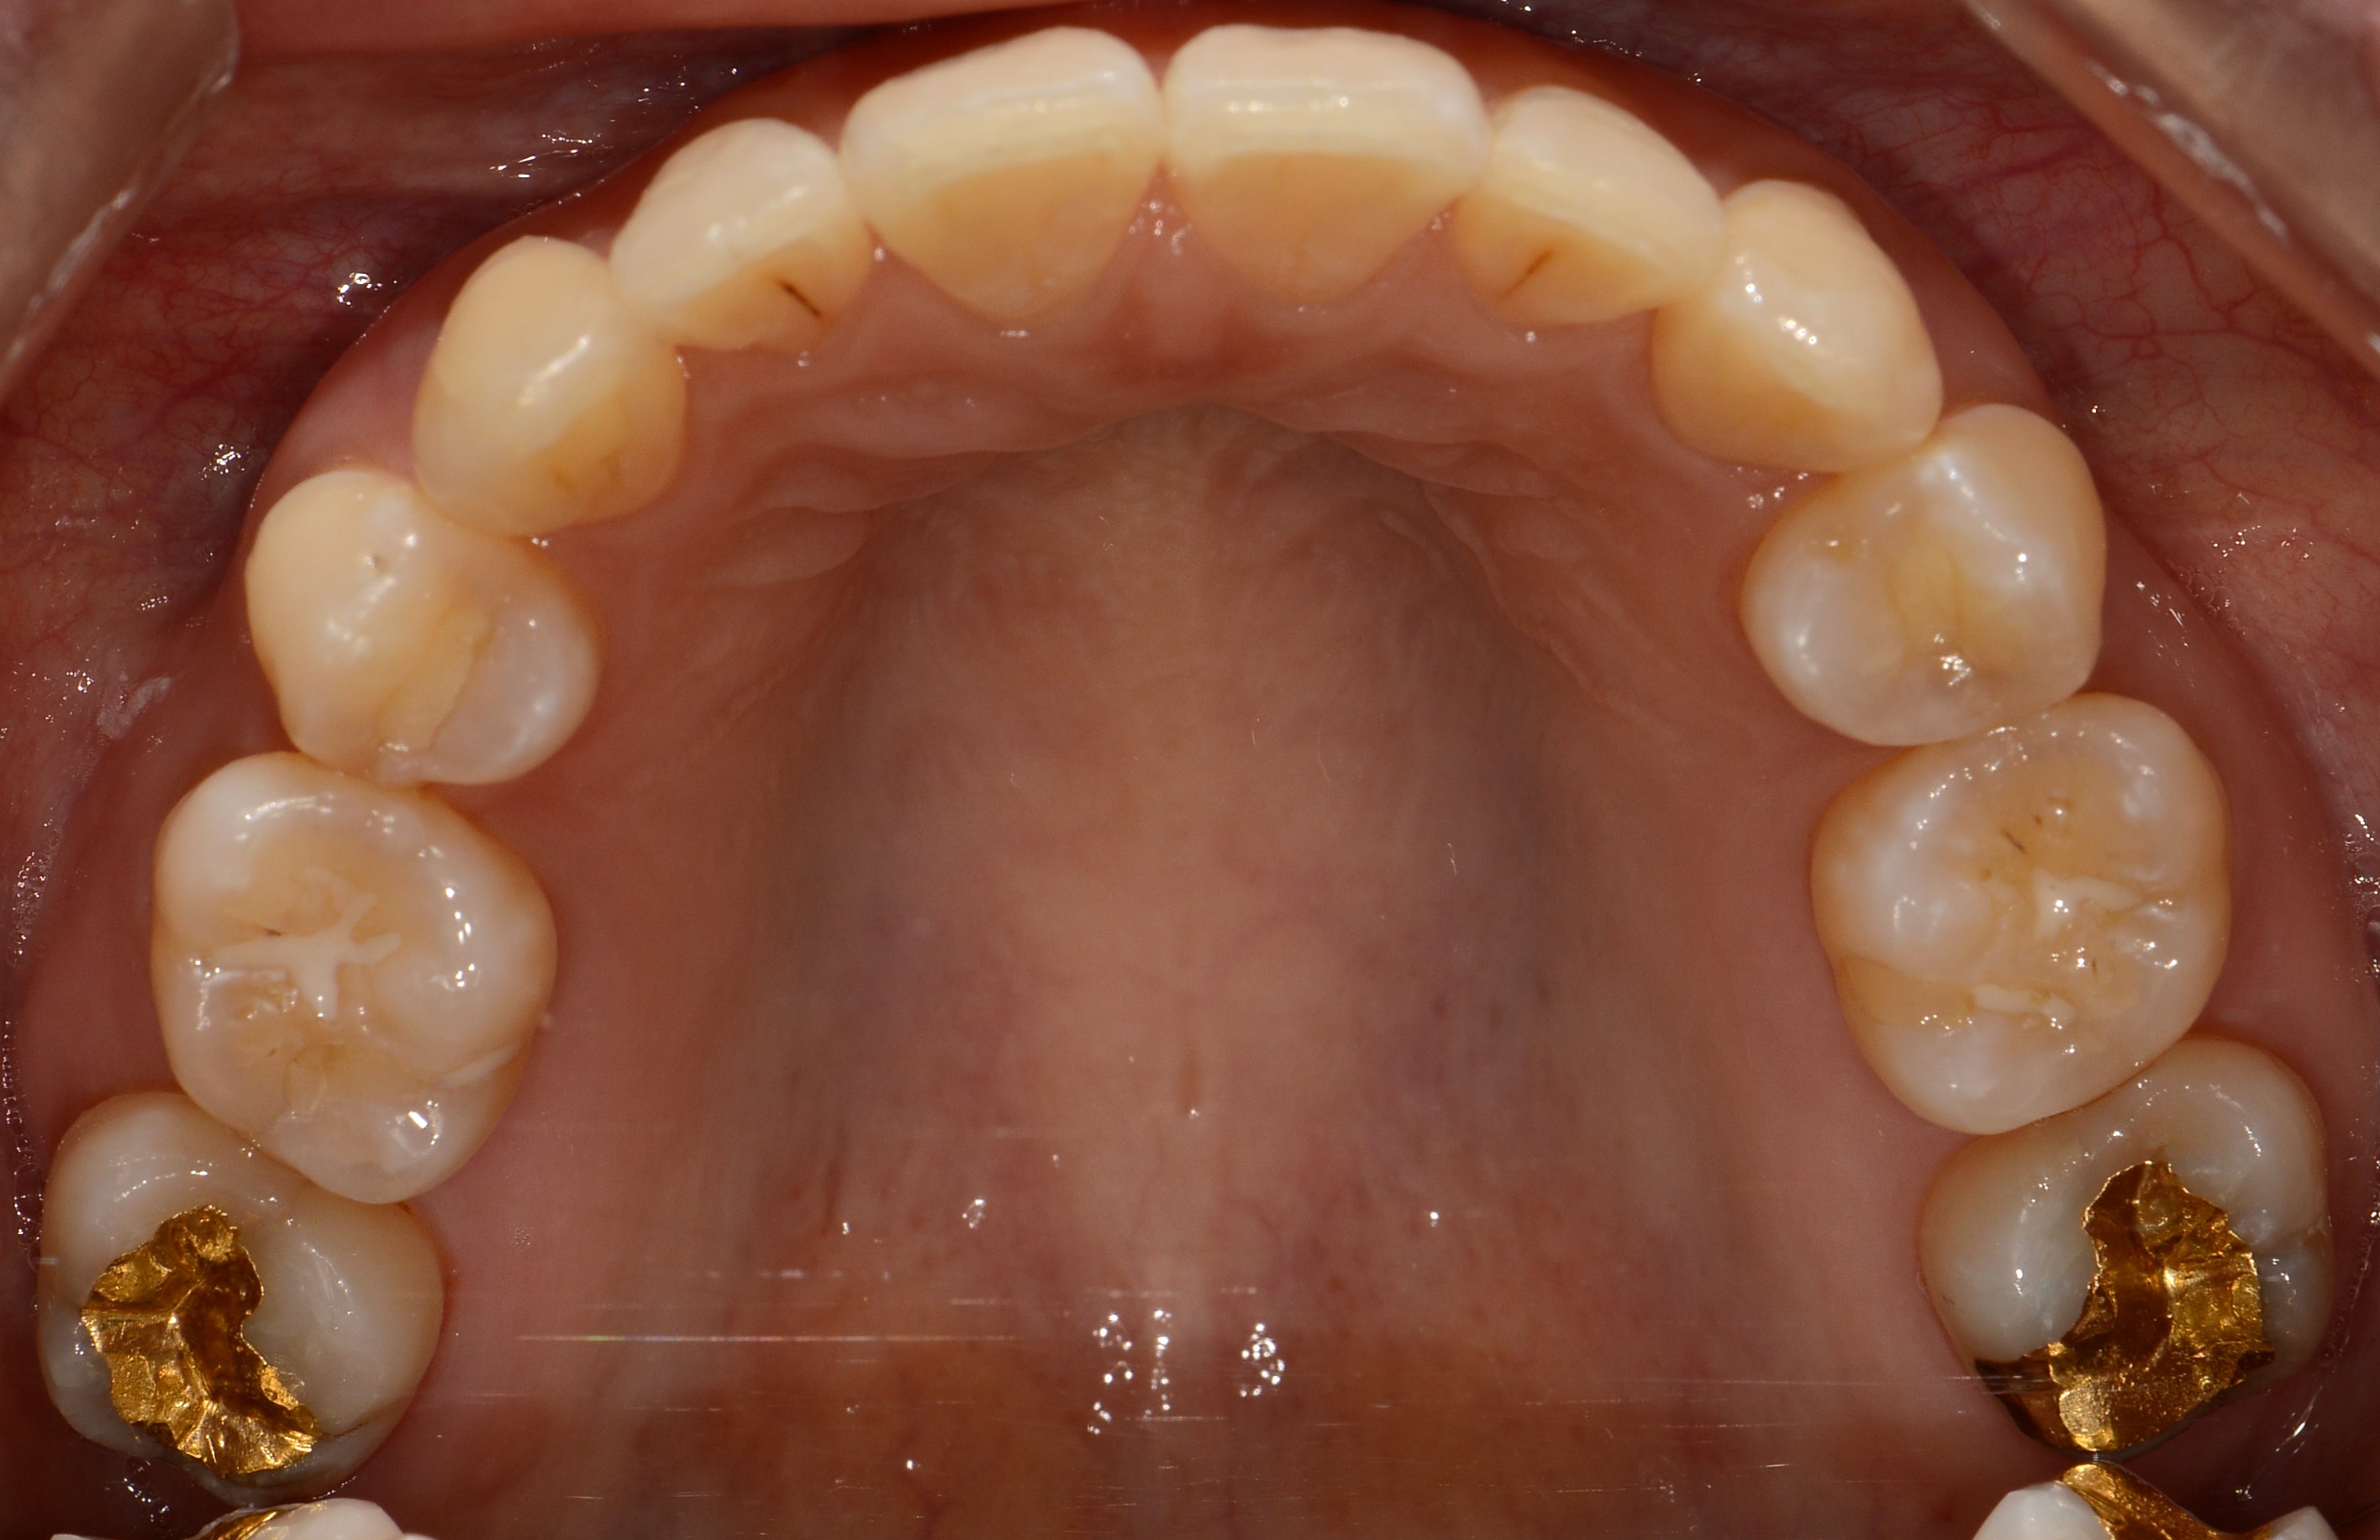

치료 후 사진입니다.